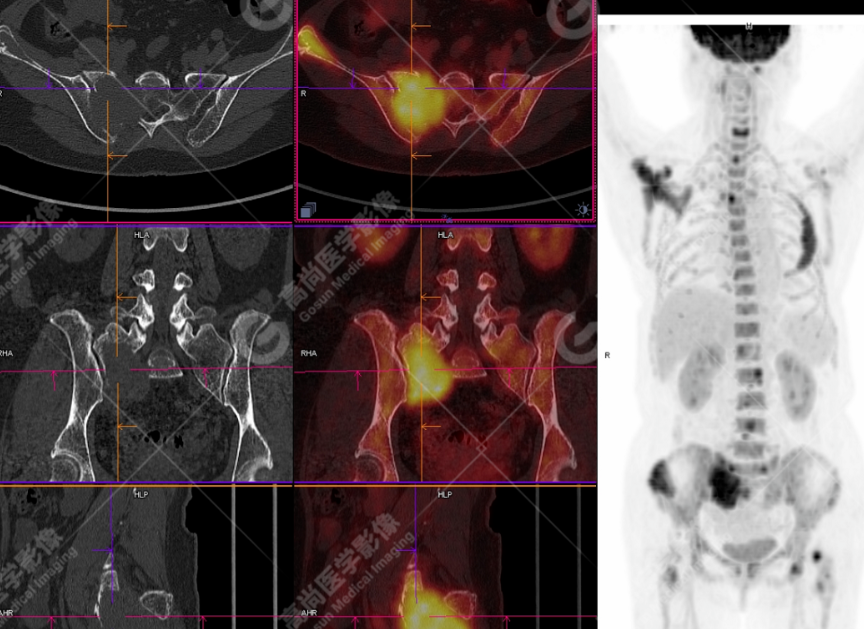

颅骨、寰椎前弓左侧份、第 6 颈椎、双侧肩胛骨(右侧为著)、左侧第 4 肋骨、第 1 胸椎、第 4 胸椎、第 2 腰椎及附件、第 4 腰椎及附件、骶骨、右侧髂骨、左侧坐骨结节、左侧股骨颈、双侧股骨小转子等均不同程度骨质吸收、破坏,其中右侧肩胛骨、左侧第 4 肋骨及骶骨右侧份软组织肿块影形成,上述病变均考虑恶性肿瘤(血液系统来源,多发骨髓瘤可能性大),建议右侧髂骨翼穿刺活检明确。

(4)PET-CT 影像表现:在溶骨性破坏区出现相重叠的 18F- FDG 高代谢区;通常呈弥漫性高代谢区。